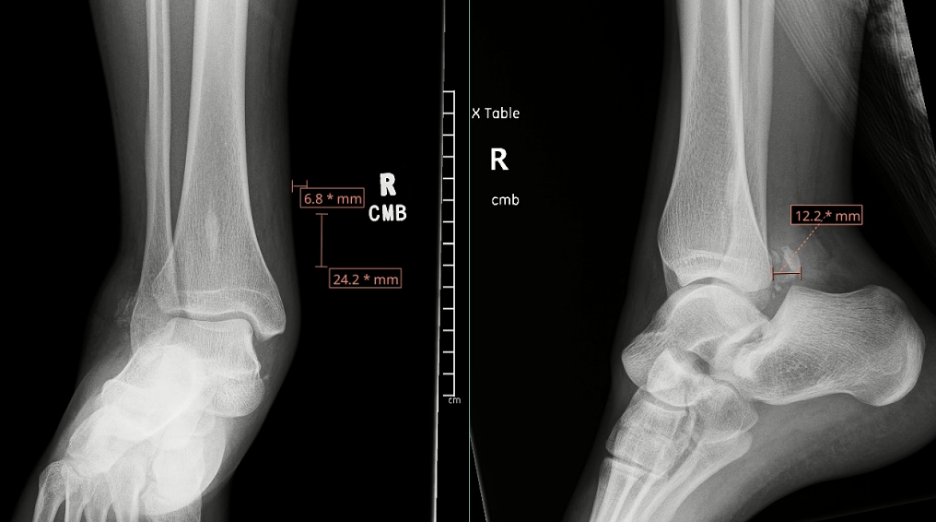

Plain film X-ray images (Figure 3 above) showed a pantalar dislocation at the subtalar (STJ), talonavicular (TNJ), and tibiotalar joints. The posterior portion of the fibula demonstrated a fracture. Computed tomography showed osseous debris in the posterior facet of the subtalar joint.

Following imaging, the patient underwent a hematoma block of the ankle and subtalar joint with lidocaine. Once properly anesthetized, we bent the knee and successfully reduced the deformity (Figure 4 above). Physicians applied a plaster splint for stability and admitted this patient for surgery the following morning. Surgeons felt the subtalar joint had residual instability. Additionally, the osseous debris in the posterior facet of the subtalar joint was difficult to ignore.